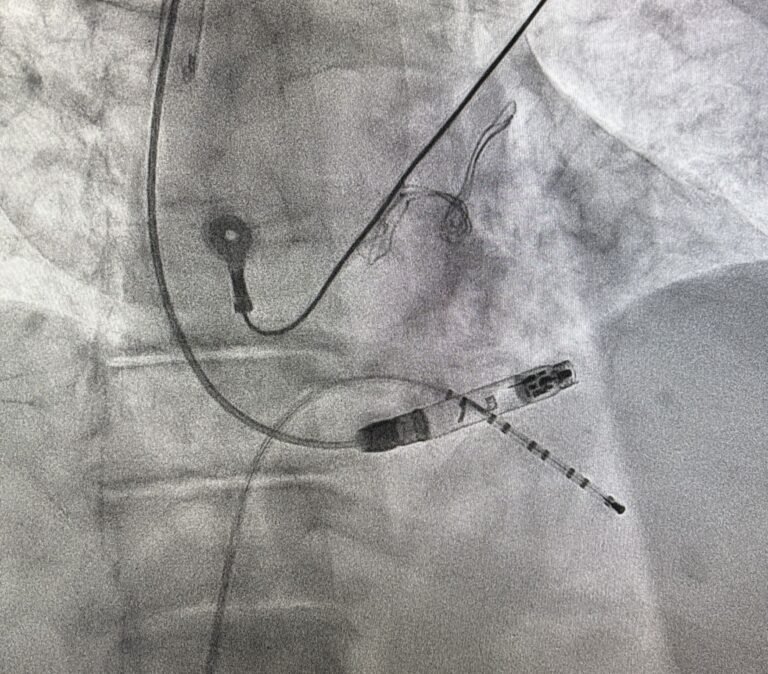

First Successful Aveir VR Implantation via Right Jugular Access After Failed Femoral Approach

Today, we successfully performed our first implantation of the Aveir VR device via right jugular access.In our center, among the 37 patients who received the Aveir VR implantation, there were…16 Luglio 2025